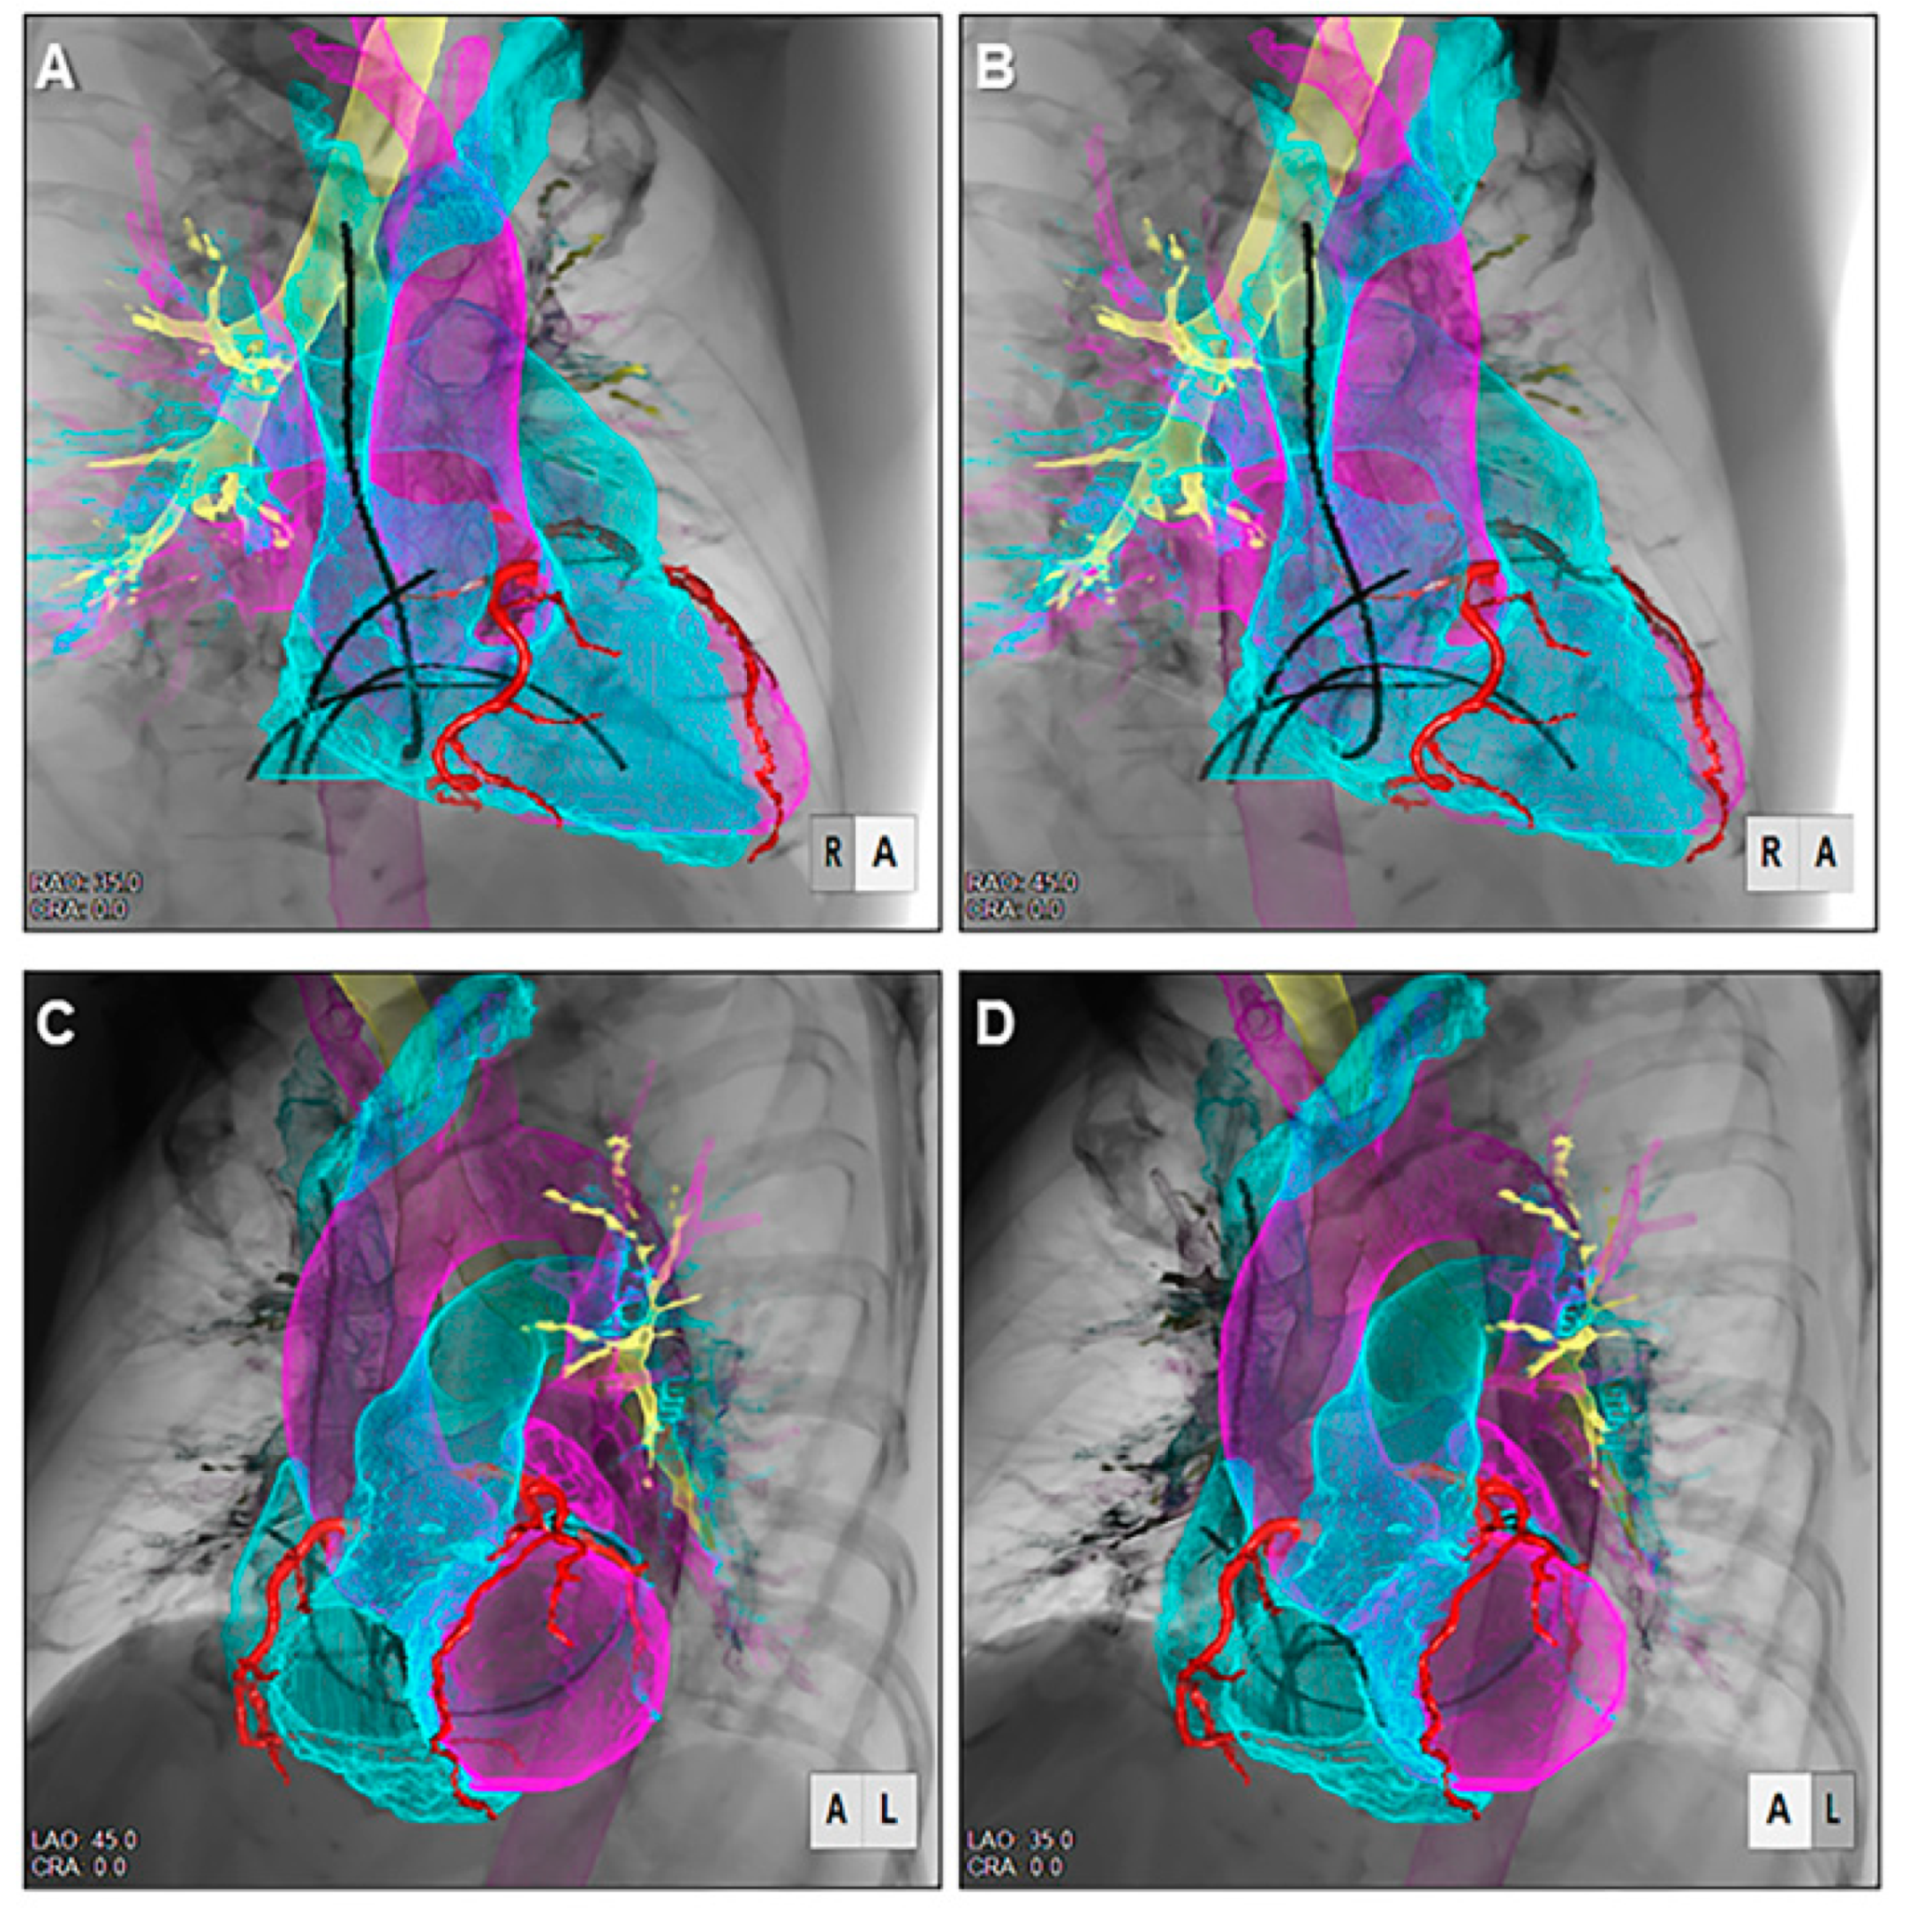

7. Advanced Application of the Three-Dimensional Imaging